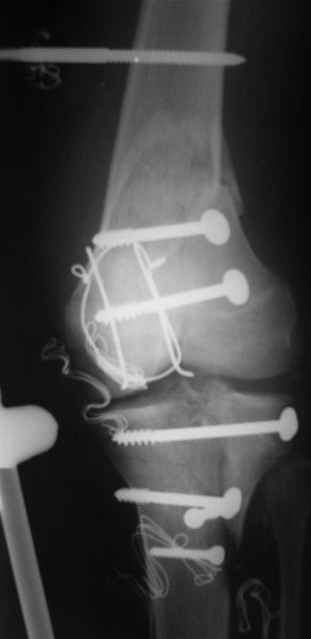

Re: открытый перелом мыщелков бедра, латерального

Вид раны на сегодня...

4 cутки после травмы.

Спасибо за комментарии. Травма тяжелая с проблематичным прогнозом для функции коленного сустава( изначально травма разгибательного аппарата с последующим частичным некрозом собственной связки надколенника и о обнажением рефиксированного фрагмента бугристости большеберцовой кости, дефектом центрального отдела суставной поверхности большеберцовой кости и медиального отдела капсулы сустава).